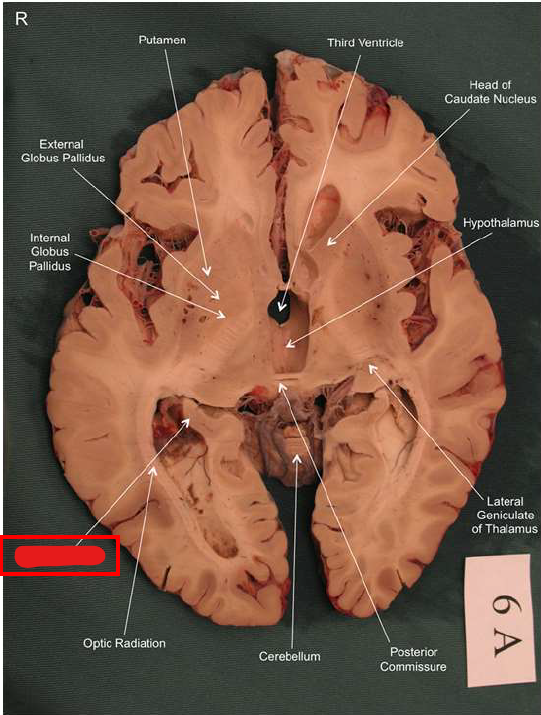

What is this?

hippocampal fornix